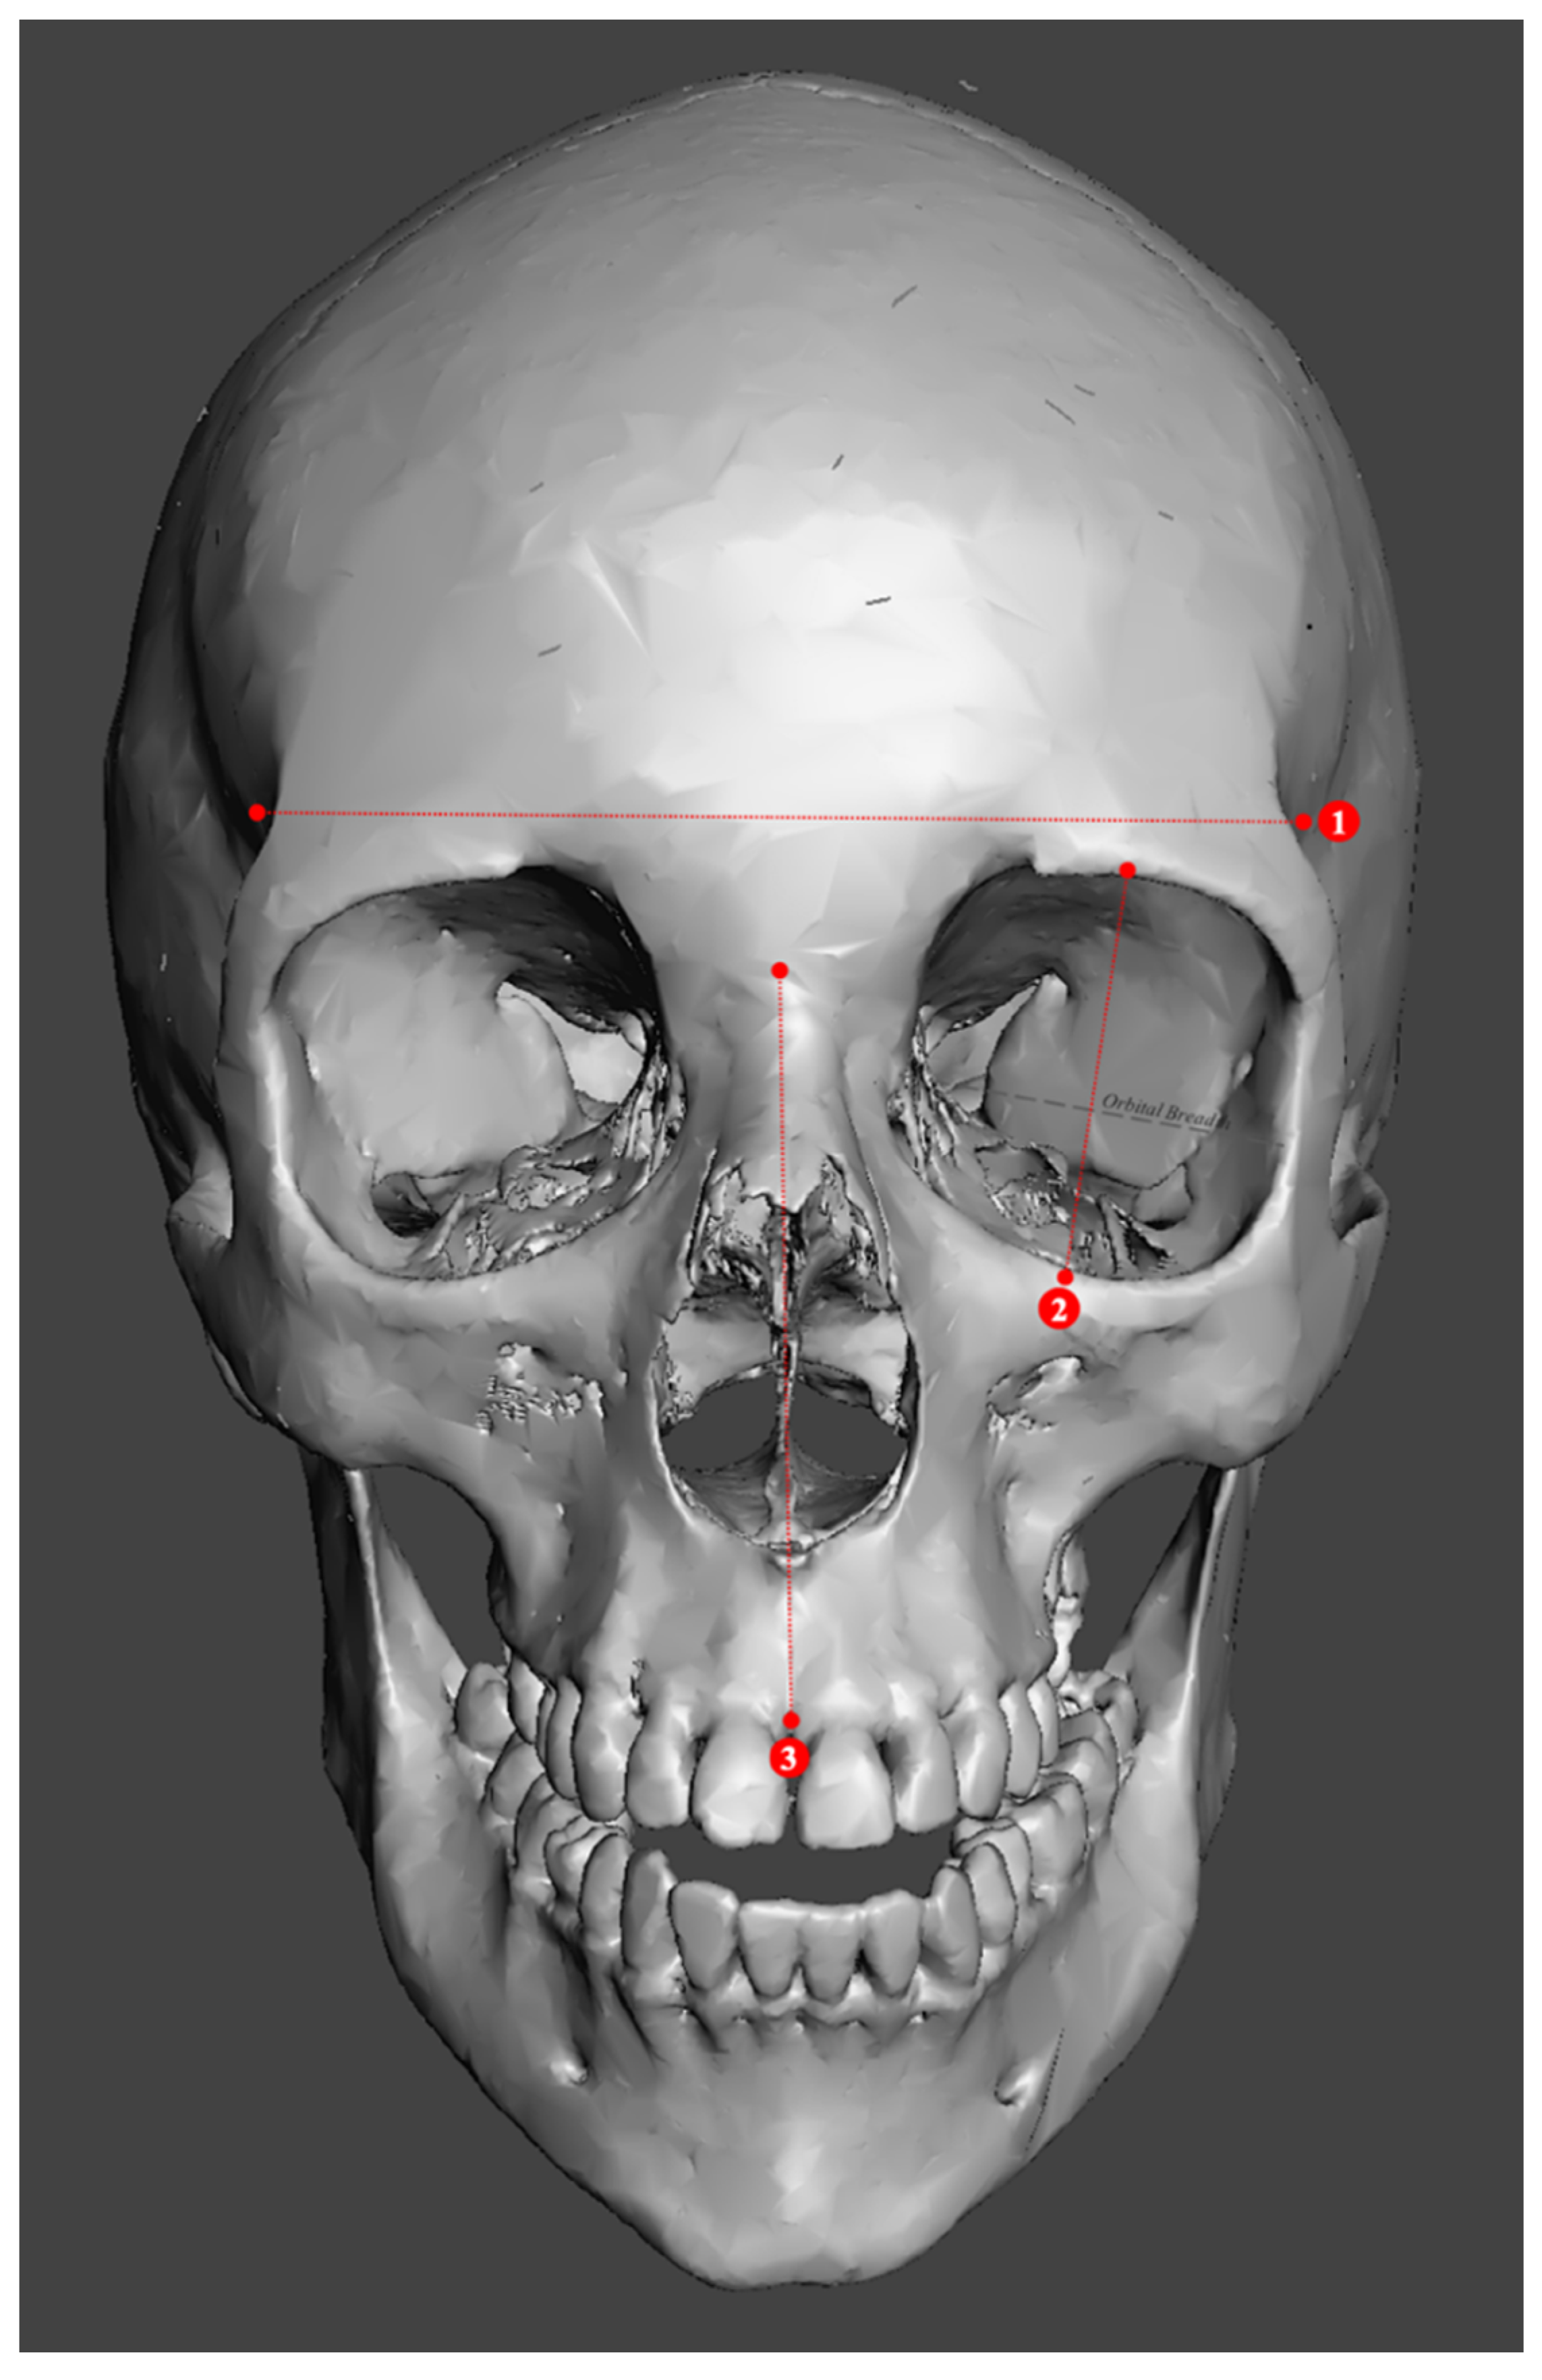

2.2. Study Sample Preparation and Data Collection

3.2. Metric Models

4.2. Metric Models